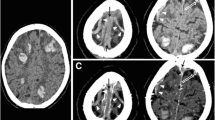

Two independent neuroradiologists with 14-year experience performed quantitative image analysis both in the DCVT group and in the control group. They were asked to measure (1) dural sinuses attenuation by tracking a round large ROI in standardized regions of the cerebral dural venous system such as posterior superior sagittal sinus, the confluence of the venous sinuses (Torcular Herophili), left and right transverse-sigmoid sinus passage, without including the adjacent bone, CSF, or dura; (2) deep venous system attenuation by drawing a round small ROI within internal cerebral veins and vein of Galen without including adjacent structures (Fig. 2).

Mean attenuation values in the different sinuses segments and deep veins in patients with dural sinuses and deep cerebral veins thrombosis. Axial unenhanced CT (a–h). (1) Dural sinuses attenuation by tracking a round ROI in standardized regions of the cerebral dural venous system: posterior superior sagittal sinus (red round ROI in c), Torcular Herophili (red round ROI in d), transverse-sigmoid sinus passage (red round ROI in d). (2) Deep venous system attenuation by drawing a round small ROI within internal cerebral veins (red round ROI in g), vein of Galen (red round ROI in h)